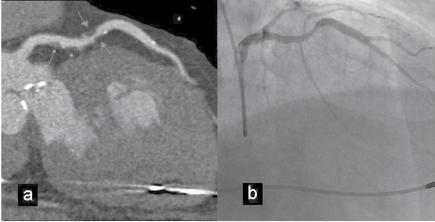

From an ECG standpoint, coronary angiography (Figure 1.1) is especially important in the acute phase for diagnosing the disease and correlating the site of occlusion with the ST‐segment deviations. It is also useful in the chronic phase of the disease. However, in the chronic phase of Q‐wave myocardial infarction (MI) the ECG does not usually predict the state of the coronary tree, because revascularization has often modified the characteristics of the occlusion responsible for the MI (Basso and Thiene 2006). Moreover, coronary angiography is insensitive for detecting minor collaterals that could attenuate ischemia. Coronary angiography does not give information about the myocardium and, thus, cannot directly assess the extent and severity of ischemia, especially in the acute phase of acute coronary syndromes (ACSs).

Figure 1.1 (A) Normal case: coronary angiography (left) and three‐dimensional CTA (right) showing normal left anterior descending (LAD, arrow) and left circumflex (LCX) coronary arteries. The latter is partially covered by the left appendix in CTA. (B) Normal case: coronary angiography (left) and CTA (right) showing a normal dominant right coronary artery (RCA). (C) An 85‐year‐old man with atypical chest pain: (a) Maximal intensity projection (MIP) of CTA with tight mid‐LAD stenosis that correlates perfectly with coronary angiography (b). (D) Similar case as (C) but with the stenosis in the proximal RCA. (a–d) CTA and (e) coronary angiography. (E) A patient with tight stenosis in the LCX before a bifurcation. (a) and (b) CTA and (c) coronary angiography. (F) These images show that CTA may also demonstrate the presence of stenosis in distal vessel branches, in this case in the posterior descending branch of the RCA. (a–b) CTA and (c) coronary angiography. (G) These images show that CTA (a, b) may delineate the length of a total occlusion and visualize the distal branches (see arrows in (b)). Collateral flow from the LAD to the RCA may be better visualized with CTA than with conventional coronary angiography (c: here only the RCA is shown). (H) A 42‐year‐old patient with a stent implanted in the LAD six months before. The patient complained of atypical chest pain and underwent CTA. The MIP images of CTA (a–c) show no significant restenosis, but some plaque formation in the left main trunk (d, circle) that was not well seen in coronary angiography (e). The degree of luminal obstruction by the plaque can be exactly measured by intravascular ultrasound (IVUS) (f). The ECG showed mildly inverted T waves in V1–V3 during follow‐up (see Plate 1 in color plates).

intervention (PCI) (Figure 1.1). CTA may provide additional diagnostic information for clinical decision‐making in contemporary stable chest pain patients with intermediate pre‐test probability for IHD (Hoffmann et al. 2017). In additional to narrowing, CTA can provide information on coronary distribution, including abnormalities in the origin and course of the arteries, and presence of coronary aneurysms. However, the accuracy of assessing the severity of coronary stenosis in highly calcified lesions and within stents is reduced.